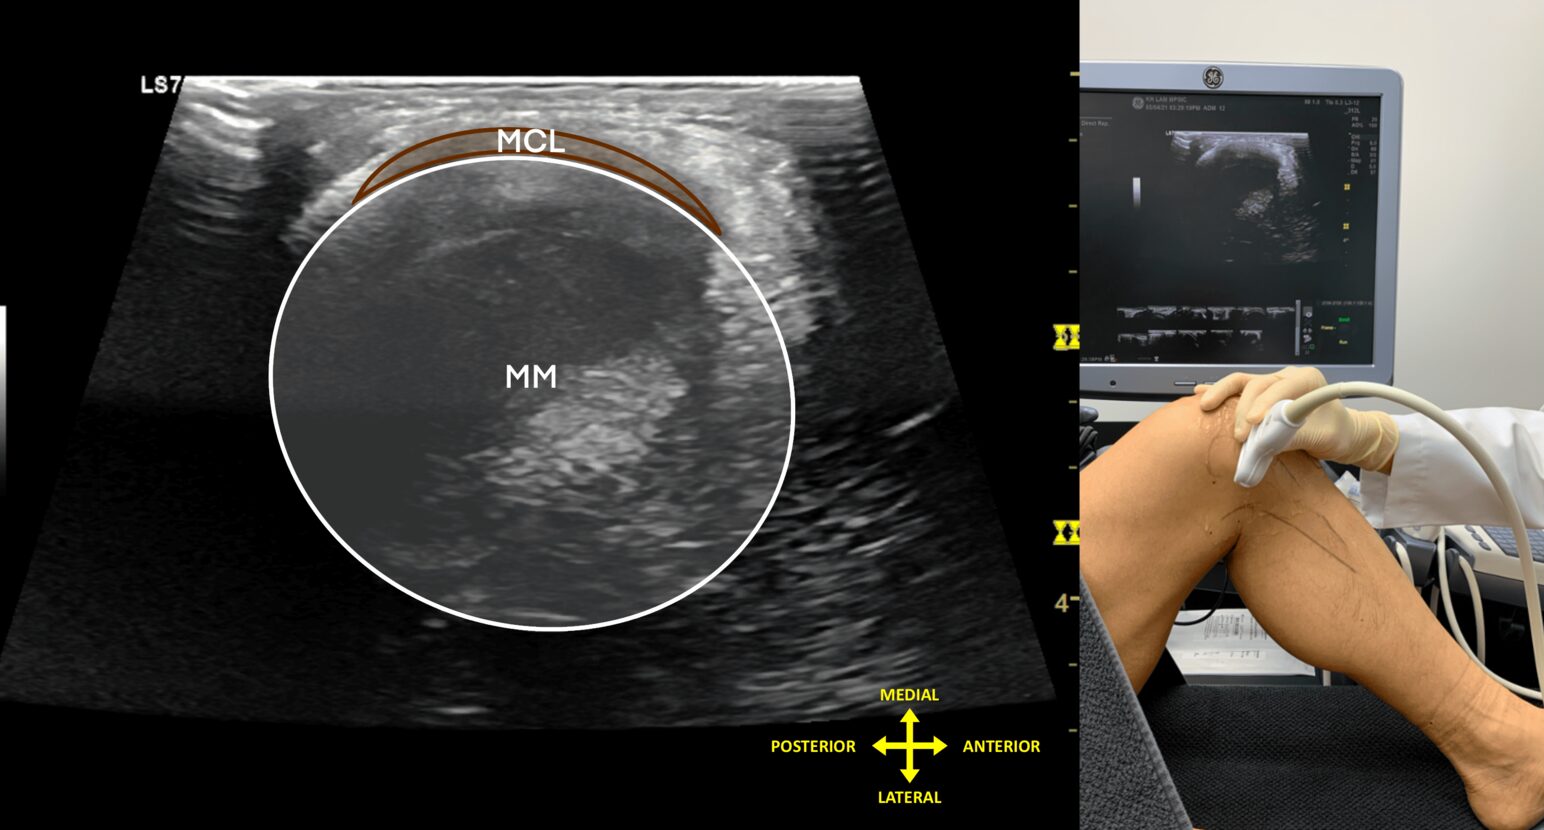

Sonoanatomy of the anterior, lateral, medial, and posterior knee, varus and valgus tests, and flexion and extension tests in different patient positions.

Provides guided protocols for diagnostic ultrasound assessment in the knee region.

Includes scans and explanations of common knee pathologies, along with dynamic assessments.

High-resolution ultrasound images, detailed anatomical illustrations, functional anatomy visuals, dynamic tests, and animations.